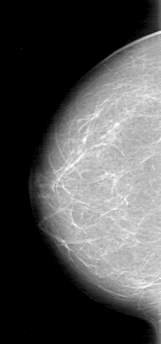

D_4048_1.LEFT_MLO

LEFT_MLO LINES 5386 PIXELS_PER_LINE 3061 BITS_PER_PIXEL 12 RESOLUTION 43.5 OVERLAY

FILE: D_4048_1.LEFT_MLO.OVERLAY

TOTAL_ABNORMALITIES 1

ABNORMALITY 1

LESION_TYPE MASS SHAPE IRREGULAR MARGINS OBSCURED

ASSESSMENT 0

SUBTLETY 5

PATHOLOGY BENIGN

TOTAL_OUTLINES 1

BOUNDARY